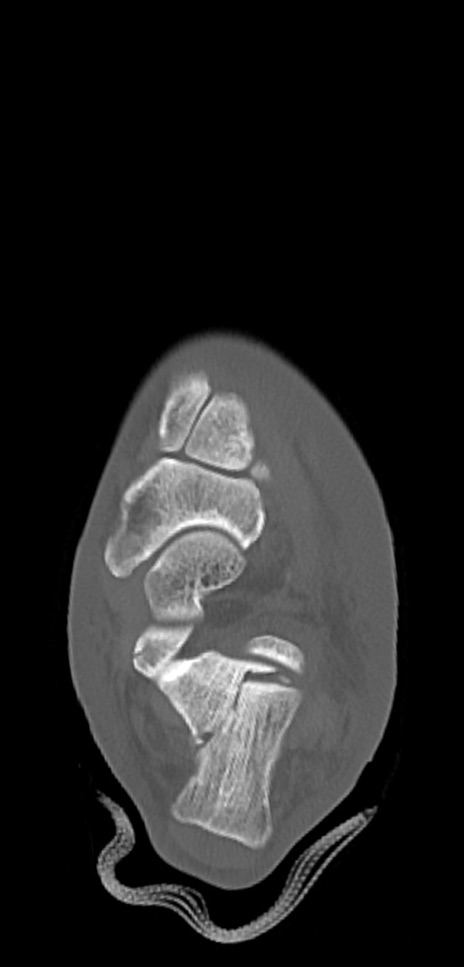

症例37 左足関節CT(横断像)

左足関節CT